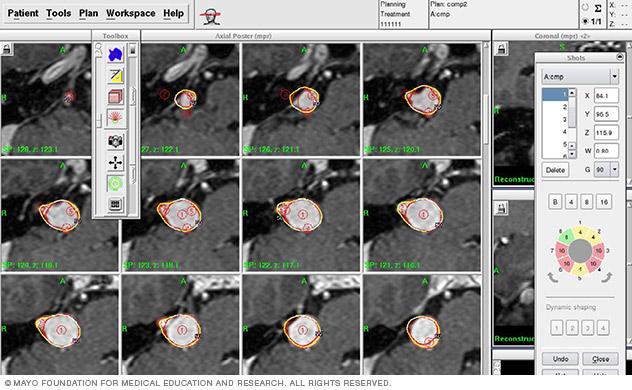

Computerized stereotactic radiosurgery radiation dose planning

3. Dose planning. The results of the brain scans are fed into a computerized planning system that enables the radiosurgery team to plan the appropriate areas to treat, dosages of radiation and how to focus the radiation beams to treat the areas.

This planning process may take an hour or two. During that time, you can relax in another room, but the frame must remain attached to your head. If you are doing LINAC stereotactic radiosurgery of the brain, typically you would be sent home during the planning process and treatment would be delivered a few days later.

3. Planning. Using the imaging scans and specialized software, your treatment team will determine the best combination of radiation beams to target your tumor or other abnormality.